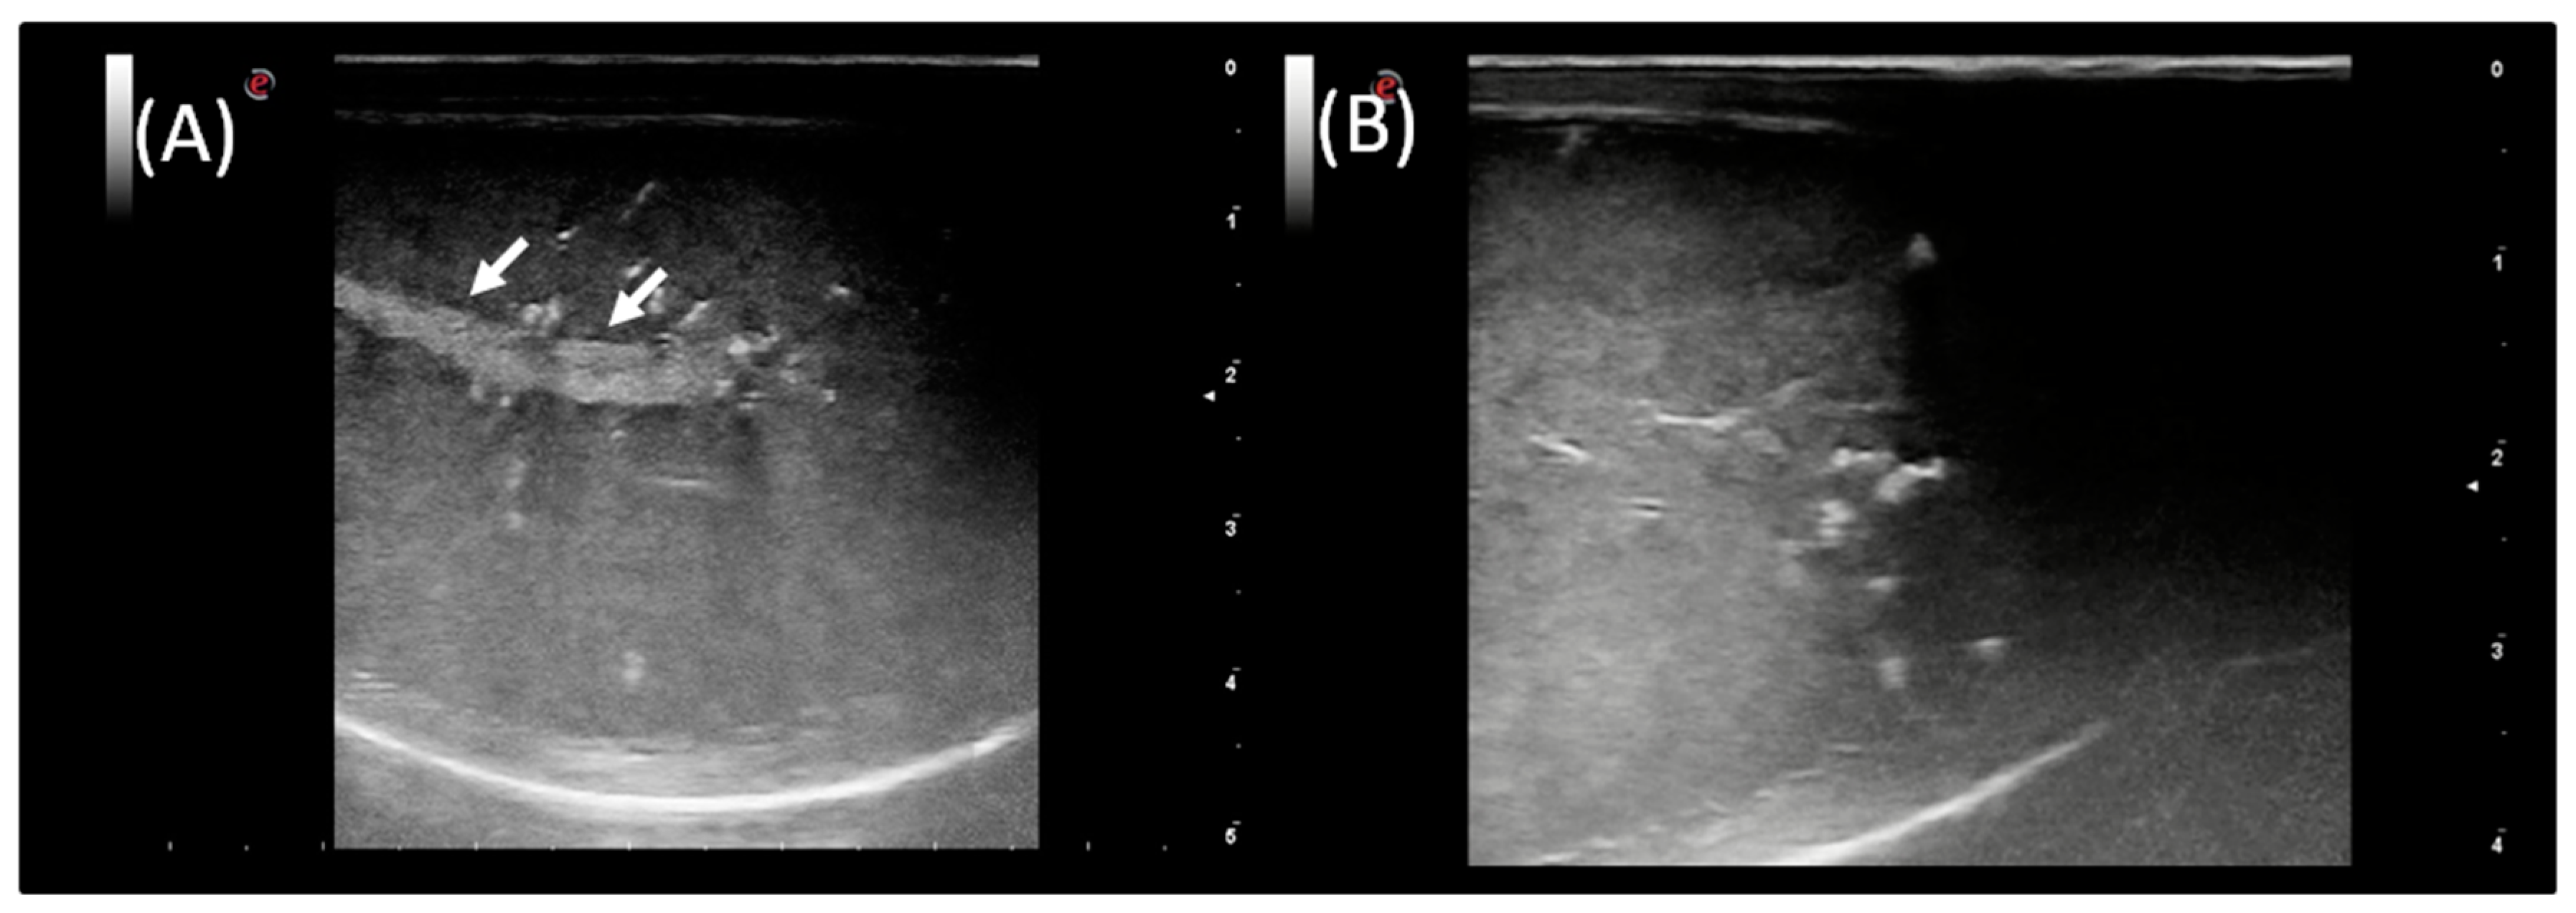

2.3. Ultrasound Examination and Doppler Application

3.3. Ultrasound Examination and Doppler Application